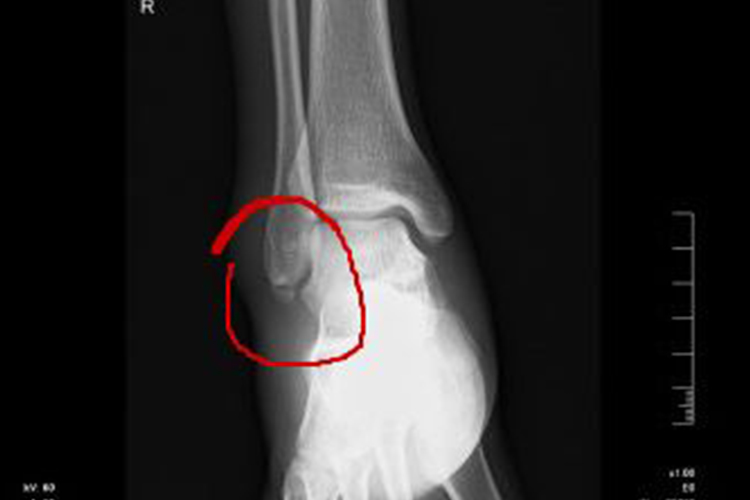

脚踝裂纹骨折属于骨折中比较轻微的一种,发生后主要的临床表现是脚踝局部出现疼痛、肿胀、皮下瘀斑,并有不同程度的运动功能障碍。检查时可在骨裂处扪到局限性压痛。

踝部轻微骨裂多由间接暴力引起,大多数是在踝跖屈时扭伤所致,也可因直接冲撞、挤压等直接暴力引起。有骨骼病变的骨组织,可在轻微的外力作用或日常活动中发生骨裂,如踝关节骨肿瘤、骨质疏松等。